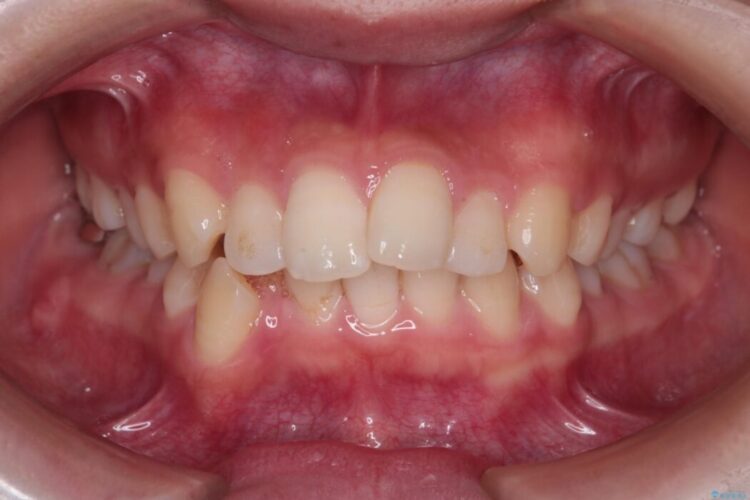

前歯から奥歯にかけて重度のがたつきを主訴にご来院された患者様です。

長年の悩みだった重度の乱れが解消され、口元の突出感もすっきり改善。見た目も機能も安定した、理想的な歯並びを獲得していただけました。